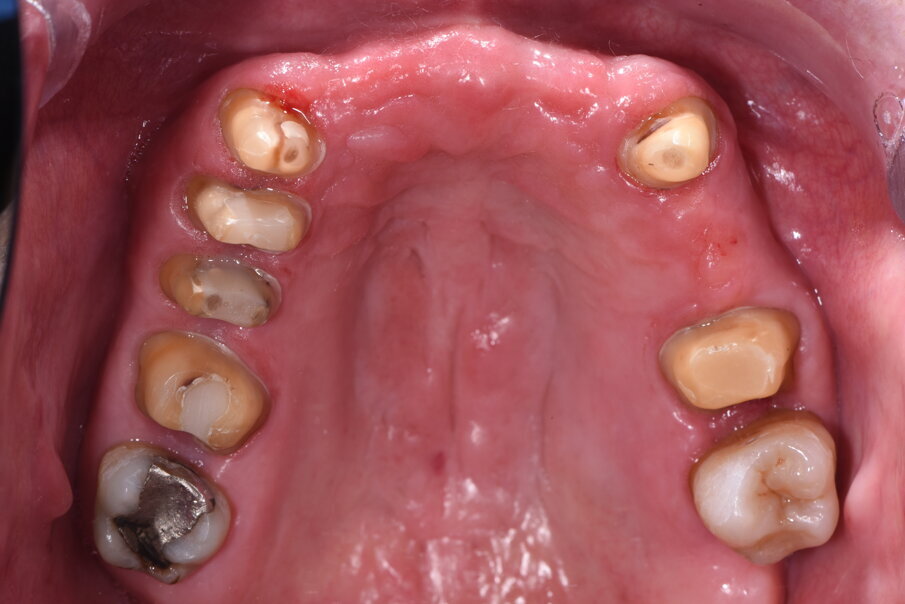

Il caso clinico descrive una situazione complessa di una paziente trattata con radioterapia 5 anni prima per un carcinoma della laringe, in conseguenza del quale era stato rimosso l’intero gruppo incisivo superiore sostituendolo provvisoriamente con una protesi parziale rimovibile stabilizzata con ganci a filo sui canini (Fig. 1). La paziente di 59 aa presentava inoltre delle protesizzazioni fisse nel quadrante I° e III° su elementi naturali, entrambe con vistose infiltrazioni e scheggiature che rendevano i manufatti incongrui. Lo stato parodontale iniziale presentava un sondaggio medio (Tab. 1) spesso associato a mobilità di vario grado e per taluni elementi era presente anche sanguinamento. All’esame obiettivo si evidenzia una complessa situazione clinica riportata di seguito in Tabella 2.

Fig. 17_Visione occlusale a preparazione degli elementi naturali ultimata in preparazione orizzontale a chamfer.

Fig. 18_Nella preparazione si devono rispettare i parametri di parallelismo, rispetto biologico del solco e arrotondamento degli spigoli per ottimizzare anche la stabilizzazione della dima chirurgica.